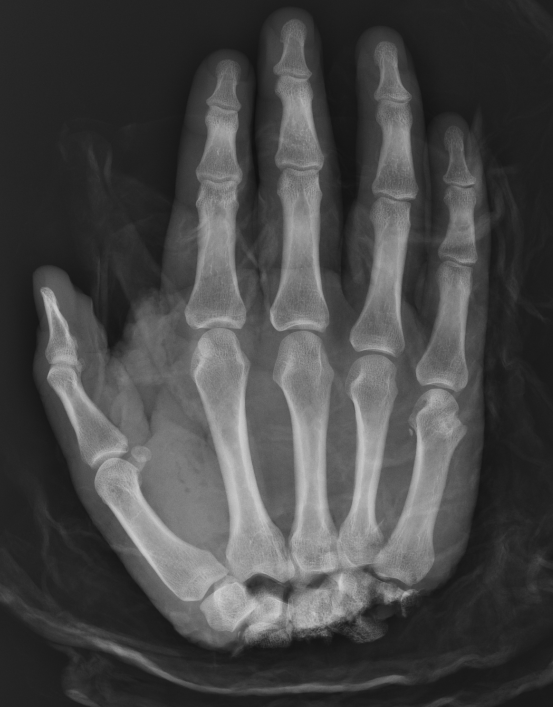

Thumb replant

![]()

Background

Thumb has first priority

A successfully replanted thumb is always better than any reconstruction

- thumb provides 40% of hand function

Level

Detipped thumb can be successful

- need dorsal veins in stump

- need 4mm of skin proximal to nail plate

- all efforts should be made to preserve thumb length